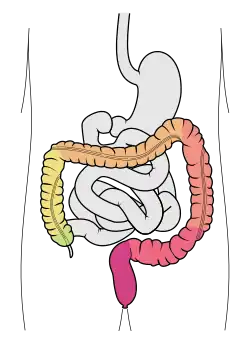

Der Dickdarm (lateinisch Intestinum crassum) ist der letzte Teil des Verdauungstraktes der Wirbeltiere und damit auch des Menschen. Er ist der Teil des Darms, der nach dem Dünndarm beginnt und an der Kloake oder am Anus endet. Seine wesentliche Funktion liegt im Transport und in der Speicherung des Stuhls. Der Dickdarm entzieht dem Stuhl Wasser und dickt ihn dadurch ein. Durch seine Fähigkeit, Natrium-, Kalium- und Chlorid-Ionen aufzunehmen oder auszuscheiden, ist er an der Feinregulation des Elektrolyt-Haushaltes beteiligt. Die Darmflora ist vor allem im Dickdarm zu finden. Erkrankungen des Dickdarms sind beim Menschen häufig: Die akute Appendizitis ist ein gängiges Krankheitsbild der Chirurgie, und Darmkrebs gehört zu den häufigsten Krebsdiagnosen.

Der Dickdarm liegt größtenteils in der Bauchhöhle, wo er die Dünndarmschlingen umrahmt. Er beginnt bei den meisten Menschen im rechten Unterbauch, wo der Dünndarm seitlich einmündet und die Krummdarm-Blinddarm-Klappe (Ileozäkalklappe, Bauhin-Klappe) bildet. Unterhalb der Einmündung endet der Dickdarm blind, entsprechend wird dieser Abschnitt Blinddarm (Caecum) genannt. An seinem Ende verengt sich der Blinddarm zum Wurmfortsatz (Appendix vermiformis), dessen Lage sehr variabel ist.

Oberhalb der Bauhin-Klappe beginnt der Grimmdarm oder das Colon (auch Kolon genannt, von lateinisch cōlon, von altgriechisch κῶλον kōlon, deutsch ‚Darm, Wurst‘[9][10][11][12]), der bis unter die Leber aufsteigt (Colon ascendens, aufsteigendes Colon), unterhalb der Leber nach links umbiegt (Flexura coli dextra) und quer durch die Bauchhöhle in den linken Oberbauch zieht (Colon transversum, auch Quercolon genannt). Hier biegt er erneut um (Flexura coli sinistra) und steigt in das Becken ab (Colon descendens, absteigender Grimmdarm), wo er anschließend S-förmig nach hinten (dorsal) zum Kreuzbein zieht (Colon sigmoideum). Dort biegt er nach unten (kaudal) um. Dort endet er und geht in den Enddarm über, der in den Mastdarm und den Analkanal unterteilt wird.[13] Für Colon wird die deutsche Bezeichnung „Grimmdarm“ sowohl in der Wissenschaft als auch in der Alltagssprache nur noch selten verwendet.[14]

Die Gesamtlänge des Dickdarms beträgt beim Menschen etwa 1,5 Meter.[15]